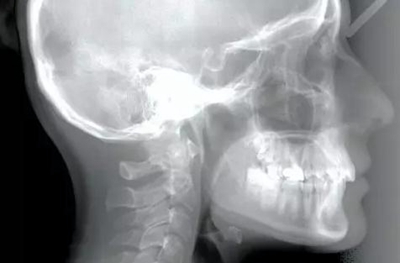

患者為19歲高加索女性,要求矯治中線不齊及上頜右側(cè)側(cè)切牙腭側(cè)異位??趦?nèi)檢查,左側(cè)安氏Ⅰ類尖牙、磨牙關(guān)系,右側(cè)安氏Ⅱ類尖牙、磨牙關(guān)系;上頜中線右偏4mm,下頜中線右偏2mm,16牙根管治療史,16及47有修復(fù)體;覆蓋5mm,覆合4mm,無橫向不調(diào)。功能檢查,顳下頜關(guān)節(jié)無明顯異常,面部及咀嚼肌不對(duì)稱。

頭影測(cè)量分析顯示,SNA為80.9°,SNB為79.5°,ANB為1.4°,SN-GoMe角為25.5°,下切牙到NA的角度為22°、距離為4mm,上頜切牙與NA角度為18°、距離為4mm,上唇在E線后5mm,下唇在E線后3mm,鼻唇角為110°。